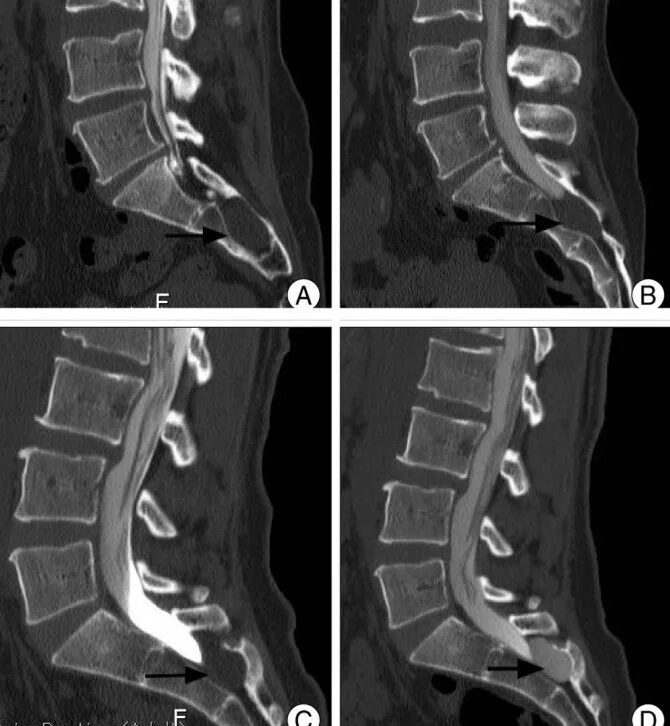

Смещение копчика